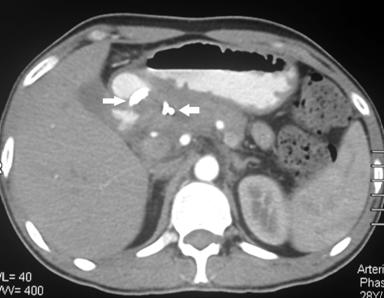

Figure 3. CTA: normal major abdominal arteries (CTA: CT angiography; CA: Celiac axis; SMA: Superior Mesenteric Artery). |

A 32 year old male patient diagnosed as alcohol related acute necrotising pancreatitis (ANP) 2 months ago, now presented with abdominal pain and early satiety. Contrast enhanced computerized tomography (CECT) showed 12 cm walled off pancreatic necrosis (WOPN) (Figure 1). Endoscopic ultrasound (EUS) revealed large WOPN and power doppler revealed vascularity in collection with pulsatile flow suggestive of blood leaking into collection (Figure 2). However, no abnormal vessel or pseudoaneurysm could be identified. CT angiography (CTA) also showed normal major abdominal arteries (Figure 3). Since patient was symptomatic, after informed consent EUS guided transmural drainage was attempted. Now there was no vascularity in collection and procedure was successfully accomplished. A 7 Fr nasocystic drain (NCD) was inserted and it drained purulent material. Patient had marked symptomatic relief but 6 hours later had severe pain and hematemesis with blood coming through NCD also. CTA revealed blood in WOPN but no abnormal bleeding vessel was identified (Figure 4). Digital subtraction angiography (DSA) also did not reveal any abnormal or bleeding vessel. The patient was managed with blood transfusion and NCD was kept patent by intermittent flushing. The bleeding subsided and the effluent from NCD cleared in 48 hours. The NCD was replaced with 10 Fr pigtail stents and CT abdomen done 3 weeks later revealed resolution of WOPN (Figure 5). The patient has been asymptomatic over a follow up period of 13 months.